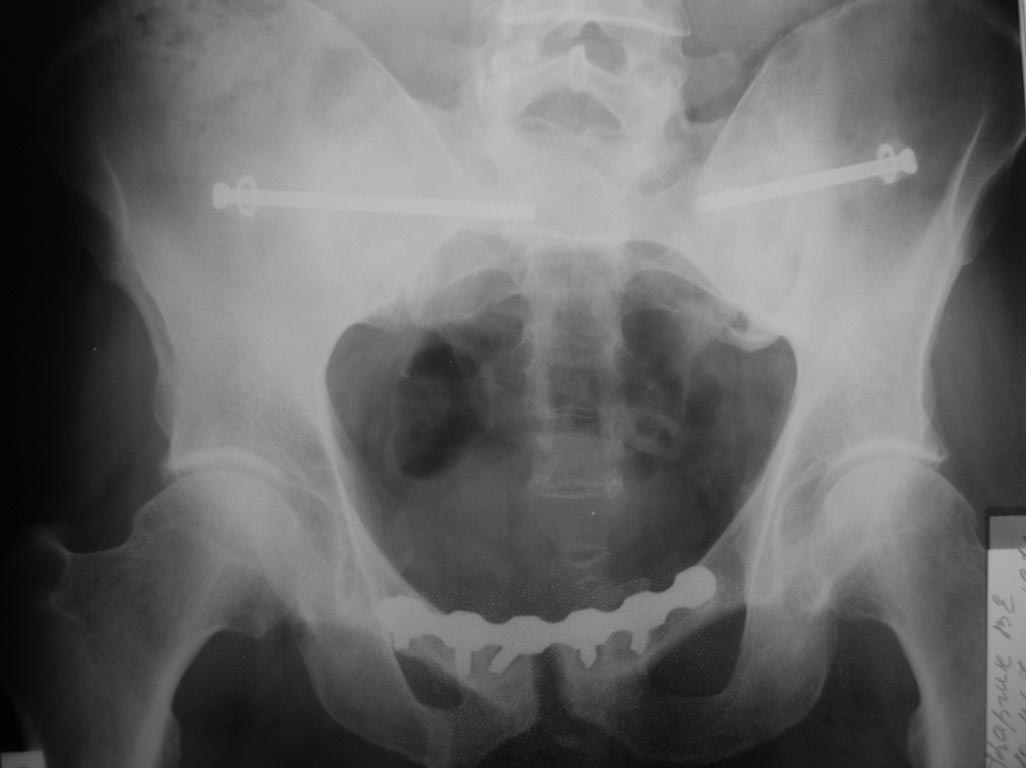

Пациент 43 лет. Травма в ноябре прошлого года. Оперирован у нас в отделении.

Послеоперационный период гладкий. В настоящий момент пациента ничего не

беспокоит, вернулся к прежней тяжелой работе (промывальщик цистерн).

Категорически настаивает на удалении металла. Проблема в том, что

оперируем таз мы достаточно часто, а вот удалять не приходилось. Вопрос:

стоит удалять, и если стоит, то не рано ли? Спасибо всем

откликнувшимся.